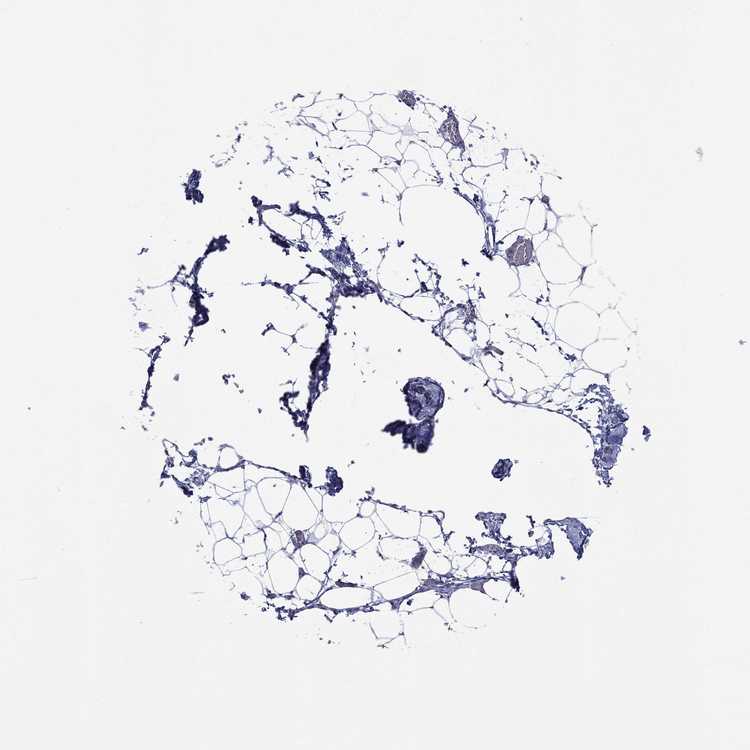

ADIPOSE TISSUE - Antibody stainingi

Antibody staining in the annotated cell types in the current human tissue is reported as not detected, low, medium, or high, based on conventional immunohistochemistry profiling in selected tissues. This score is based on the combination of the staining intensity and fraction of stained cells.

Each image is clickable and will lead to virtual microscopy that enables deeper exploration of all samples and also displays staining intensity scores, fraction scores and subcellular localization as well as patient and tissue information for each sample.

Antibody HPA042433Antibody HPA074225Antibody CAB026404

Adipocytes Not detectedNot detectedNot detected